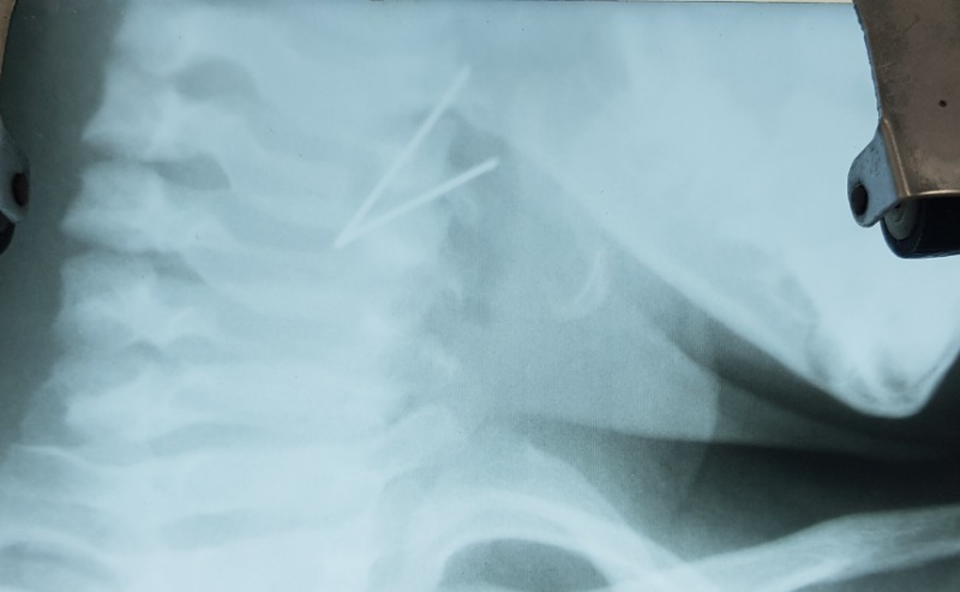

Trẻ nhập viện trong tình trạng nằm nghiêng cổ về một bên phải, không xoay sang trái được do đau và khó nuốt. Các bác sĩ cho chụp X-quang cổ thì phát hiện hình ảnh cản quang hình chữ V ở hạ họng.

Đoạn kim loại nhìn thấy qua kết quả chụp X-quang.